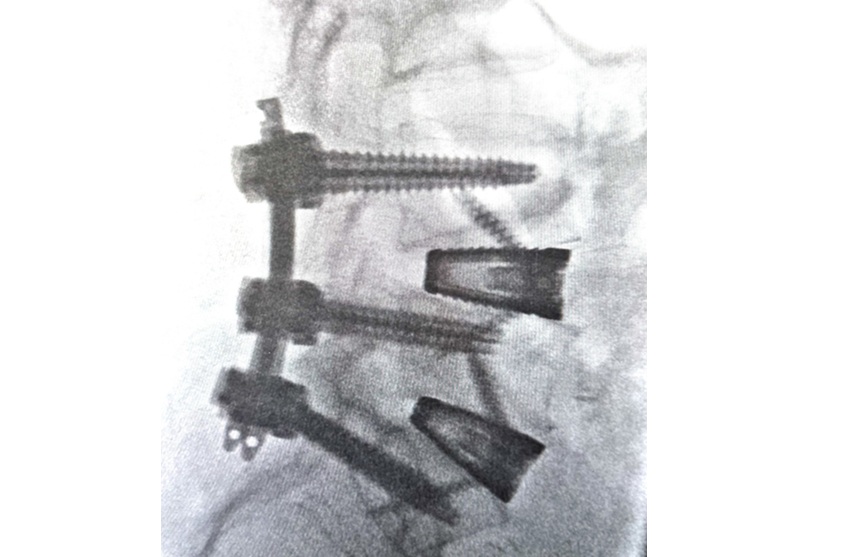

Ventana A is designed to facilitate the race to fusion and deliver improved outcomes for surgeons and patients. The unique hinged architecture of the Ventana family of implants is designed to maximize bone graft volume and containment throughout implantation. Through a specialized 3D printing process, Ventana A is engineered to enable surgeons to realize the full potential of the ALIF procedure, by restoring segmental alignment and stability, minimized titanium density, providing optimal load sharing to mitigate potential subsidence risk and improved visualization.

The first case was performed by Dr. A.J. Rush III at Texas Spine Consultants in Addison, TX. Dr. Rush shared: “The Ventana A system delivers a clinical advantage to everyday challenges for spine surgeons. The large graft window allows for maximal graft delivery as well as improved visualization for fusion assessment and distributes load across the entire surface to reduce subsidence risk. Having used the instrumentation in both lab and clinical settings, I can attest to Ventana A’s ability to offer a best in class ALIF solution.”

Dr. Rory Mayer a neurosurgeon practicing at Texas Spine & Scoliosis in Austin, TX said: “Ventana A is truly a bone graft delivery vessel. It has everything needed to maximize fusion potential for my patients: porous 3D printed titanium interbody, a large opening to facilitate bone graft placement, and a hinged lid to contain the bone graft and prevent graft from migrating from the interbody device during insertion into the disc space.”